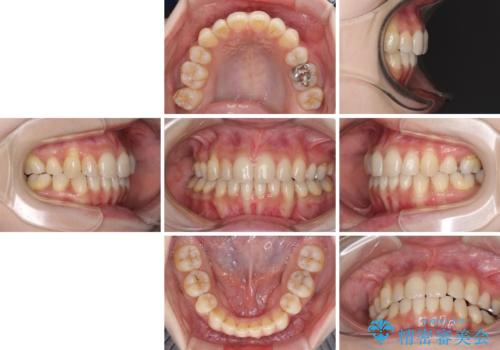

- 上下前歯の叢生を気にして来院された患者様です。

費用を抑え、期間もあまりかけずに治療をしたいとのことで、インビザライン・ライトを用いて矯正治療を行うこととしました。

インビザライン・ライトは、製作できるアライナーの枚数に制限があるため、移動可能な量に限りがあります。

一方で、半年程度で治療を終えることができるため、軽度の歯列不正の患者様には大変お勧めです。